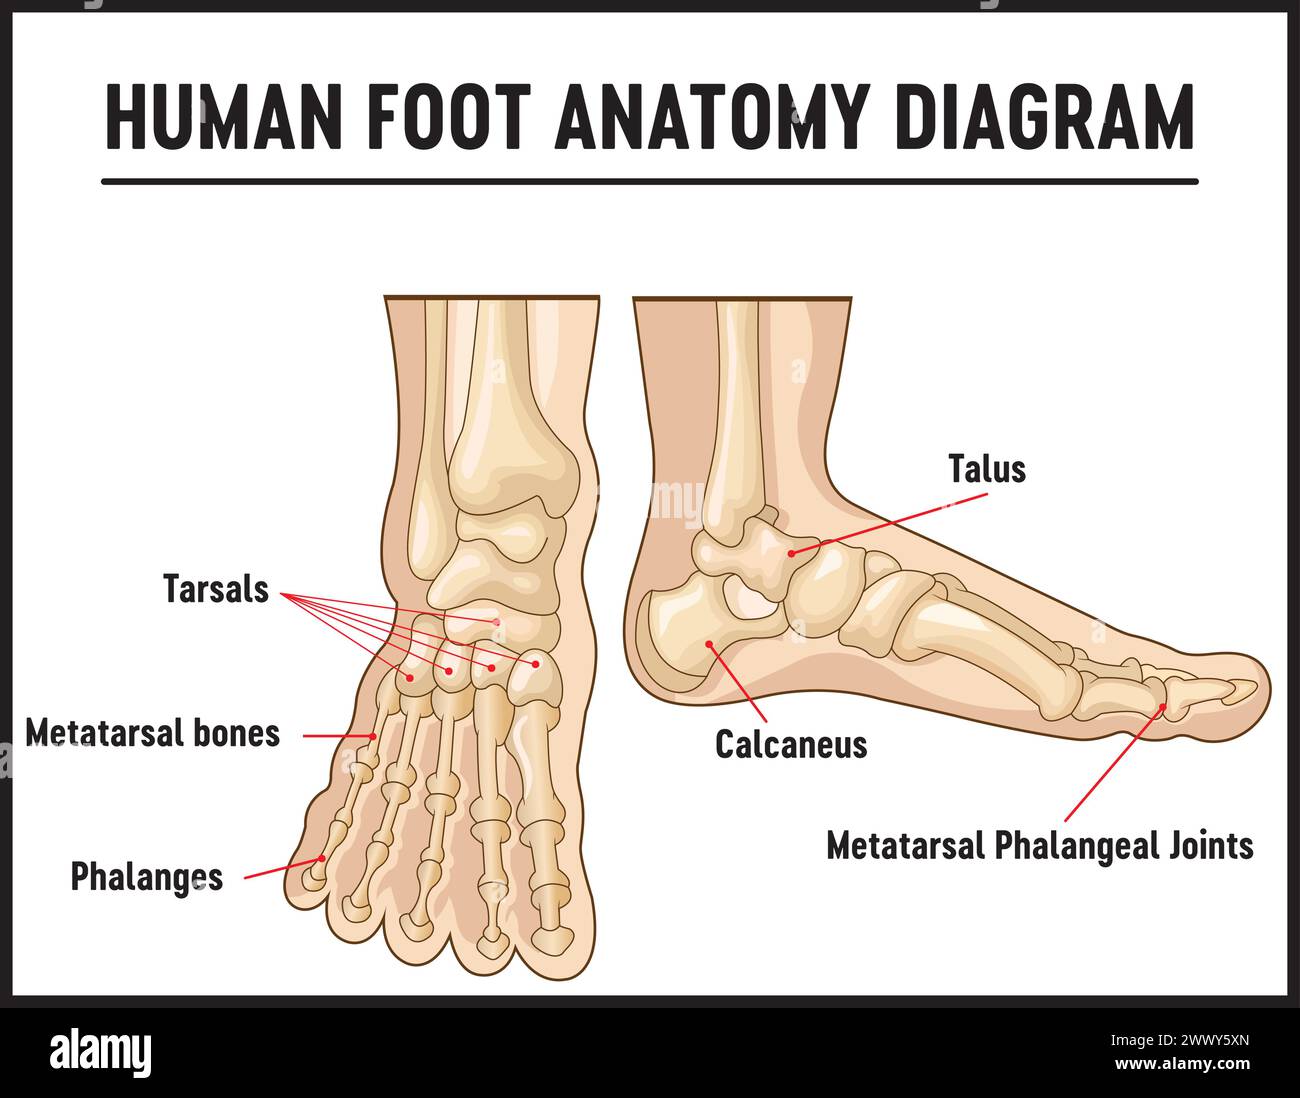

RF2WWY5XN–Os du pied humain avec le nom et la description de tous les sites. Vue supérieure. Anatomie humaine. Illustration vectorielle isolée sur un fond blanc.

RF2WNN754–Illustration médicale des principales parties des os du pied en vue antérieure, avec annotations.

RF2J65WT4–Anatomie du pied. Pied humain avec le nom et la description de tous les os et sites. Vue de dessus et vue latérale. Arcs des pieds. Anatomie du squelette. Vecteur

RF2R3WKY1–Illustration médicale des principales parties des os du pied en vue latérale, avec annotations.